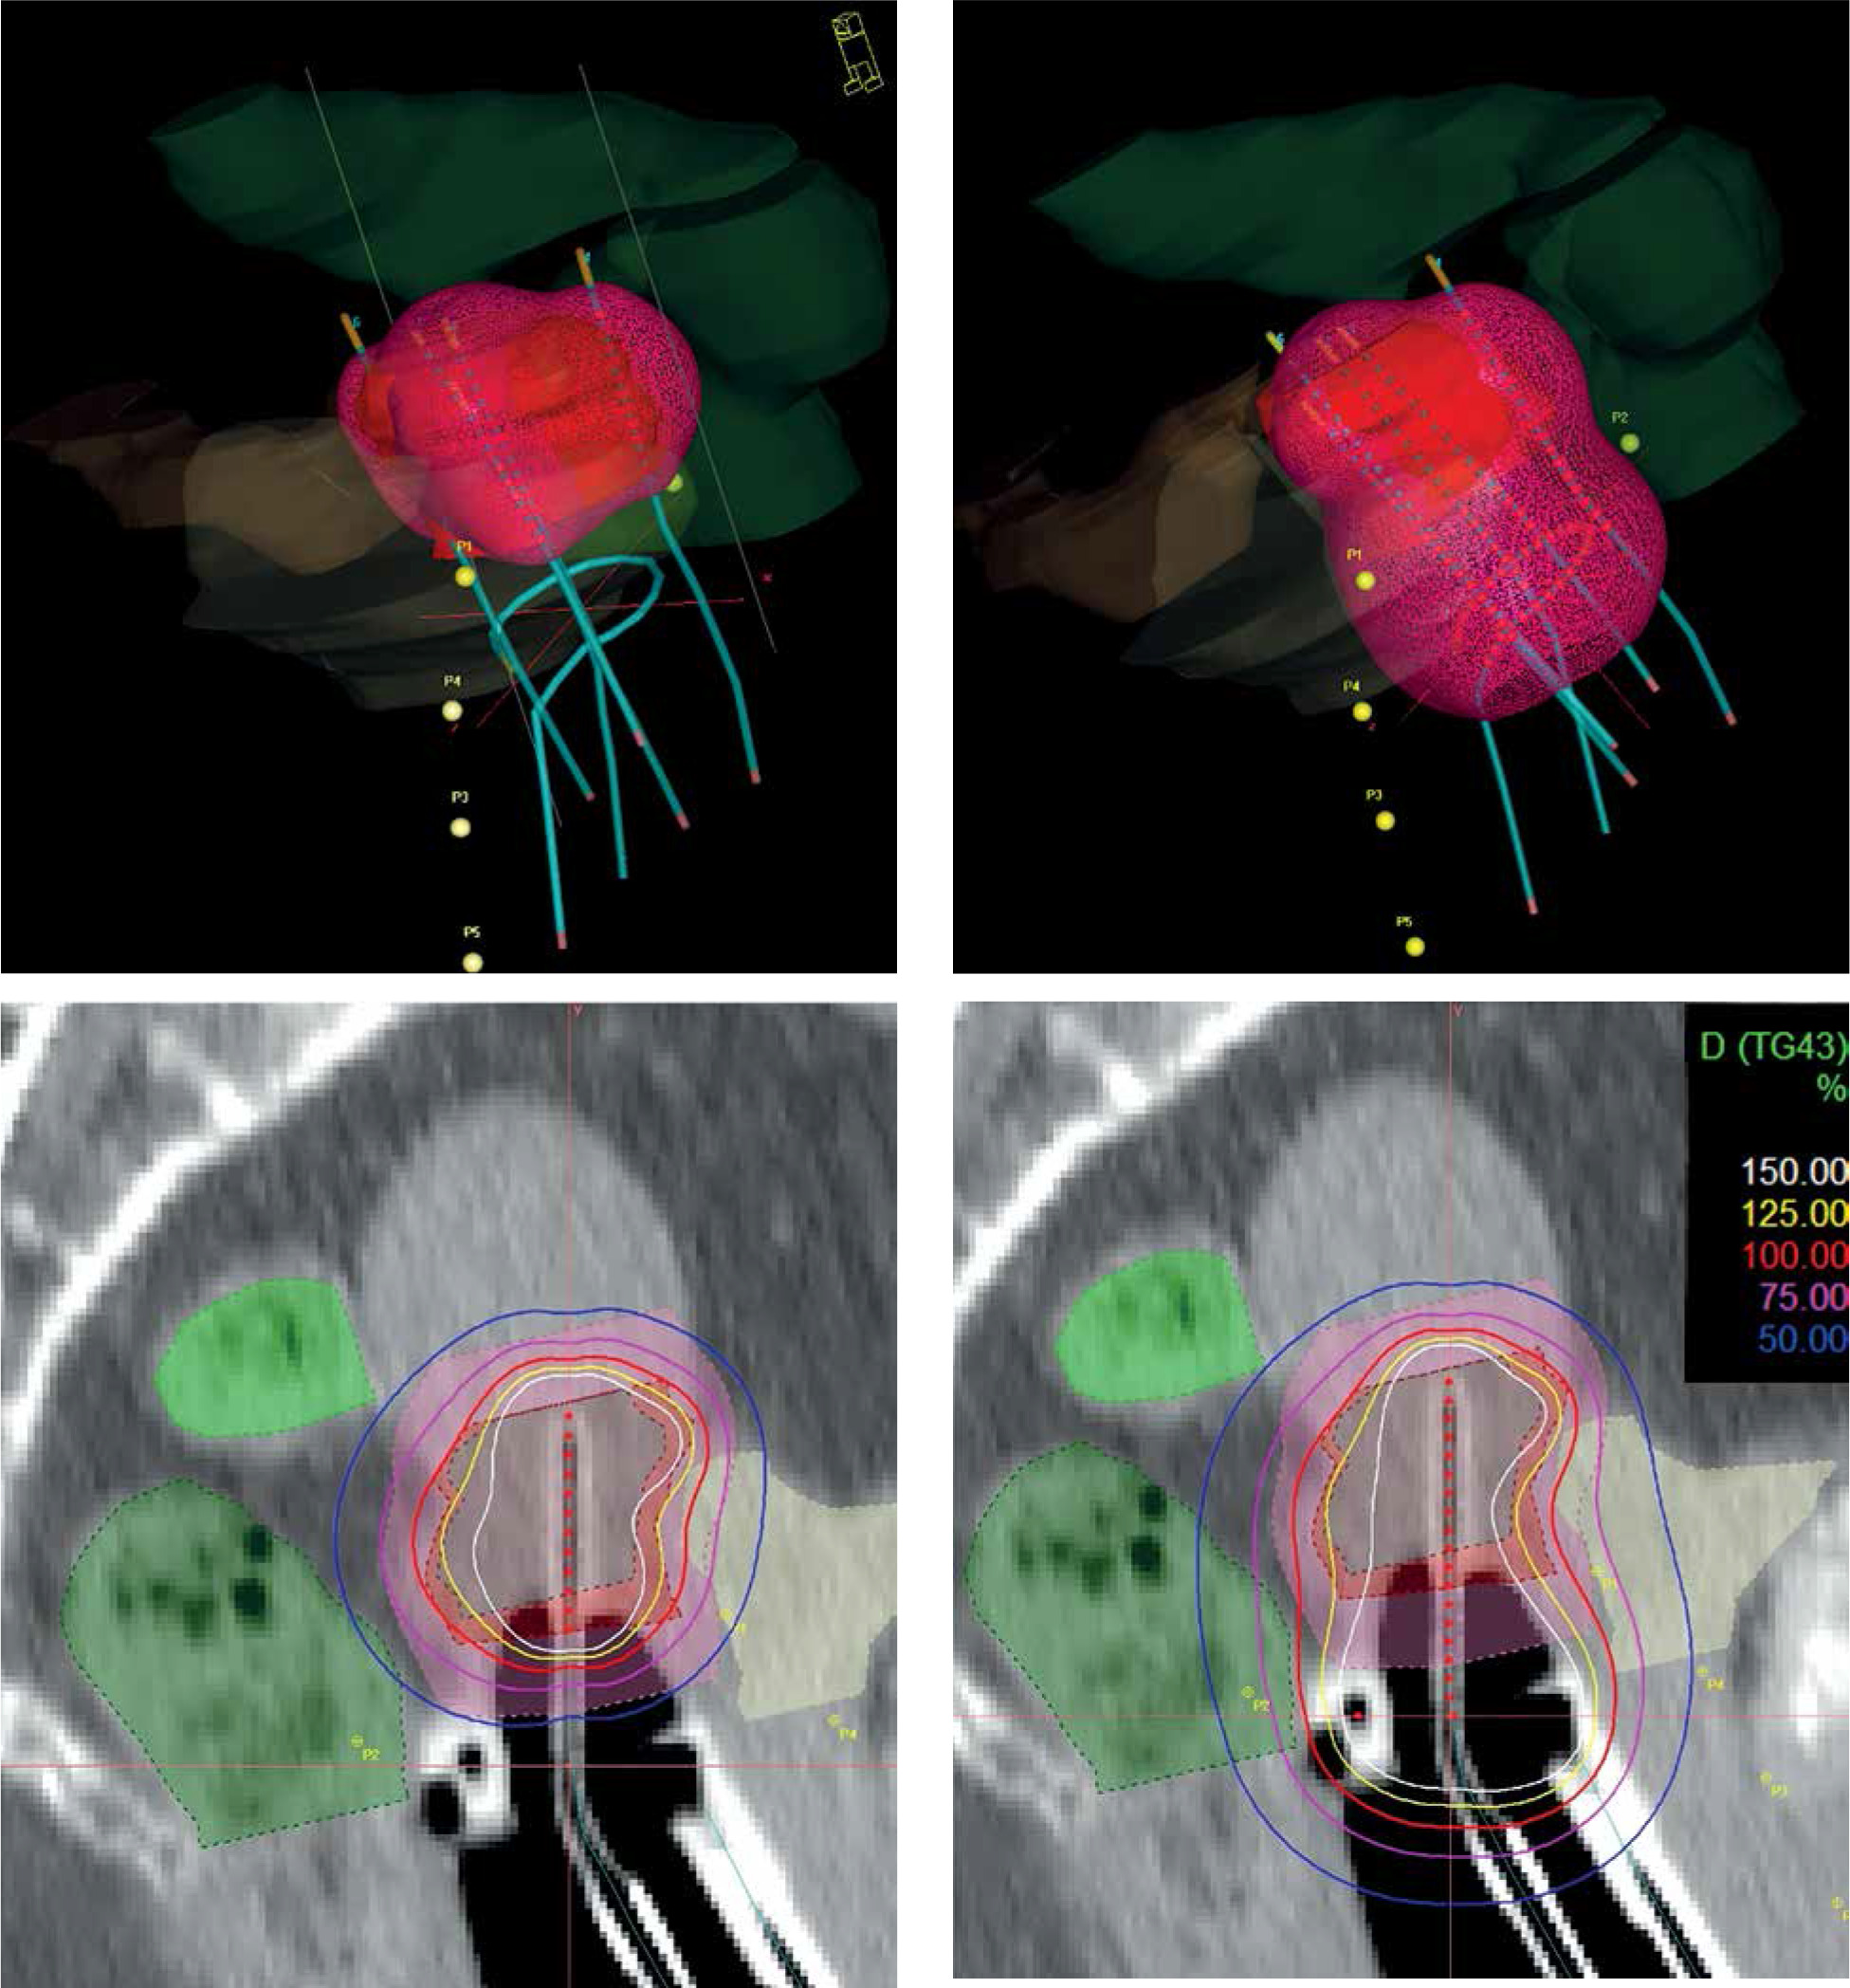

Fig. 1

Isodose surface (light red) of the prescribed dose (top) and dose distribution (bottom) without (left) and with using active dwells in the ring/ovoid of the applicator (right). Pink – IR-CTV; Red – HR-CTV; Grey – GTV; Yellow – bladder; Dark green – rectum; Light green – sigmoid

In the era of advanced imaging modalities, special IS-IC applicators with the opportunity of oblique needles and inverse dose optimization methods, there is no strong evidence available for implementing one approach over another. Tanderup et al. recommended dose planning aims and dose prescription in image-guided cervical BT [45]. However, these conclusions were based on the clinical evidence of treatment plans using the traditional pear-shape spatial dose only. Earlier, the same team tried to de-escalate the vaginal dose by decreasing dwell times in R/O and increasing it in tandem/needles [27]. The aim was to maintain the target dose while reducing the dose to the surface of the vagina to be < 140% of the physical fractional BT dose corresponding to a total EQD2 of 85 Gy. The R/O loading was reduced from 51% to 33% of total loading, which resulted in a reduced dose to ICRU recto-vaginal point by a mean of 4 ±4 Gy EQD2, and D2 doses to the bladder and rectum were reduced by 2 ±2 Gy and 3 ±2 Gy, respectively. In the current study, we achieved the total dose de-escalation of the critical tissues, as source loading in the R/O channel of the applicators was reduced to zero in cases where residual tumors did not involve the vagina. This approach simply follows the basic rule of BT that active dwell positions have to be inside or on the surface of the target volume. This technique results in a highly conformal tumor-shape dose distribution around the target volumes, breaking the rules of the conventional pear-shape dose (Figure 1).

While dose coverage of the target volumes is similar to using active R/O, the EQD2 total D2 dose to the bladder, rectum, sigmoid, small bowel, and vaginal wall were reduced by 14.1 Gy, 17.3 Gy, 5.6 Gy, 2.9 Gy, and 39.1 Gy, respectively. However, the dose to the IR-CTV was smaller without loading the R/O (D98 were 60.8 Gy using inactive, and 63.9 Gy with active R/O); these dose plans fulfilled the GEC-ESTRO (EMBRACE II study) and ABS recommendations in the same degree, i.e., 96%. In terms of residual GTV, the D90 non-significantly increased with inactive R/O (97.2 Gy vs. 95.5 Gy). Loading R/O shifts higher doses to the direction of R/O, where there is no GTV, and accordingly, unnecessarily increases the dose to OARs. The loading patterns also illustrate this effect. The tandem dominates the contribution to TRAK between the tandem and needles without R/O loading (53.2% vs. 40.8%), and these shifts to a harmonized distribution with R/O activation (Figure 2). Dose to points A is not interpretable, because of the proximity of IS needles. With the same level of homogeneity, inactive R/O results in almost 2 times higher dose conformality of the target volumes (COIN: 0.62 vs. 0.38).

Basically, the distance of the R/O source path from HR-CTV and from OARs is a good starting point to decide the activation of R/O. If the surface of the R/O part of the applicator touches the inferior border of HR-CTV, the former distance is 5-10 mm, depending on the applicator used. Especially in the case of a narrow vagina, an air gap can exist between R/O and the surface of HR-CTV (Figure 1), which may affect the use of vaginal component. It strongly influences dosimetric parameters, mainly dose conformality of the plans. If after dose optimization the dose exposition is higher to an OAR than to HR-CTV, an alternative dose plan is recommended without activation of R/O as well as evaluation of the fulfilment of dose recommendations in both the plans. The necessity of loading R/O strongly depends on an individual anatomy of a patient. Of note, in case of tumors with vaginal involvement, when HR-CTV includes a portion of the vagina, source dwell positions in R/O (in HR-CTV) has to be activated accordingly the basic rules of BT. However, majority of residual tumors of the cervix does not involve the vagina. In this case, the R/O part of the applicator can be only a template for IS needles, or a fixation tool for the intra-uterine tandem.